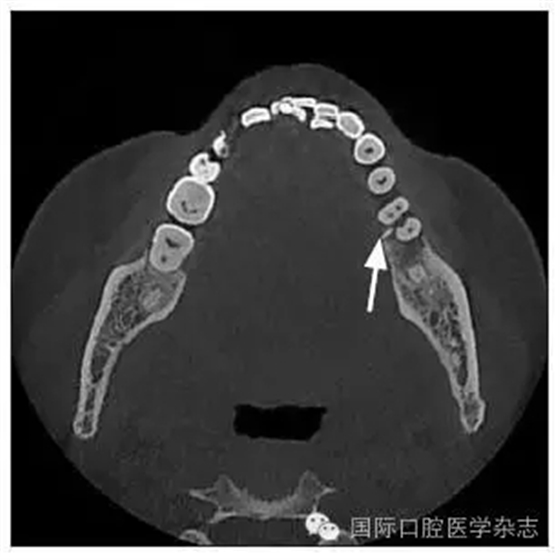

患者,女,42歲,因牙痛就診于中南大學(xué)湘雅醫(yī)學(xué)院附屬??卺t(yī)院牙體牙髓病科。臨床檢查為左側(cè)下頜第一磨牙遠(yuǎn)中齲,根尖壓痛和扣痛及頰側(cè)深牙周袋,牙髓電活力檢查陰性,近中根尖放射透明影。X線檢查根分叉區(qū)有不透明突起,扁形,

1.8 mm寬、8 mm長(圖1~3)。

圖3 CT頰舌切面觀

Fig 3 CT buccolingual section view